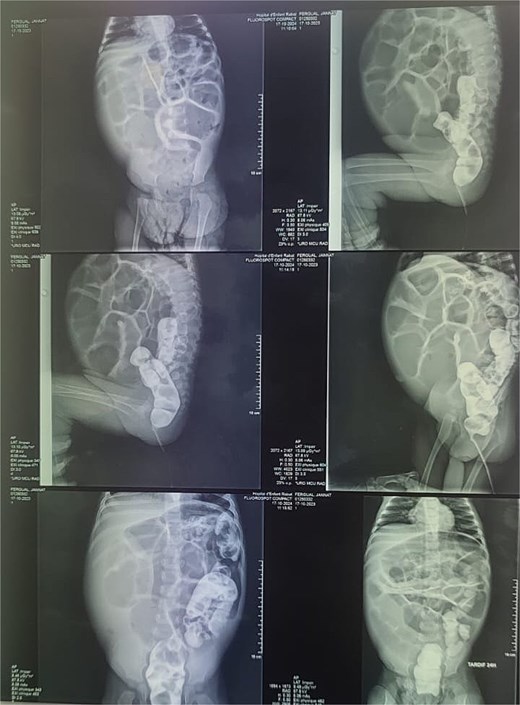

Reviewing the medical record of the patient, she underwent variable blood tests that were negative mostly except for ionogram disturbances due to malnutrition and dehydration. An abdominal X-ray was performed at each episode of hospitalization, that revealed intestinal-type hydroaeric levels and gastric stasis (Fig. 1) then a digestive fibroscopy with multiple biopsis as well as eosogastroduodenal transit were run out suggesting gastritis. A barium index (Fig. 2) was also performed on his last hospitalization suggesting a small bowel obstruction which also appeared on the Enteroscan (Fig. 3).

X-ray image showing intestinal-type hydroaeric levels and gastric stasis.